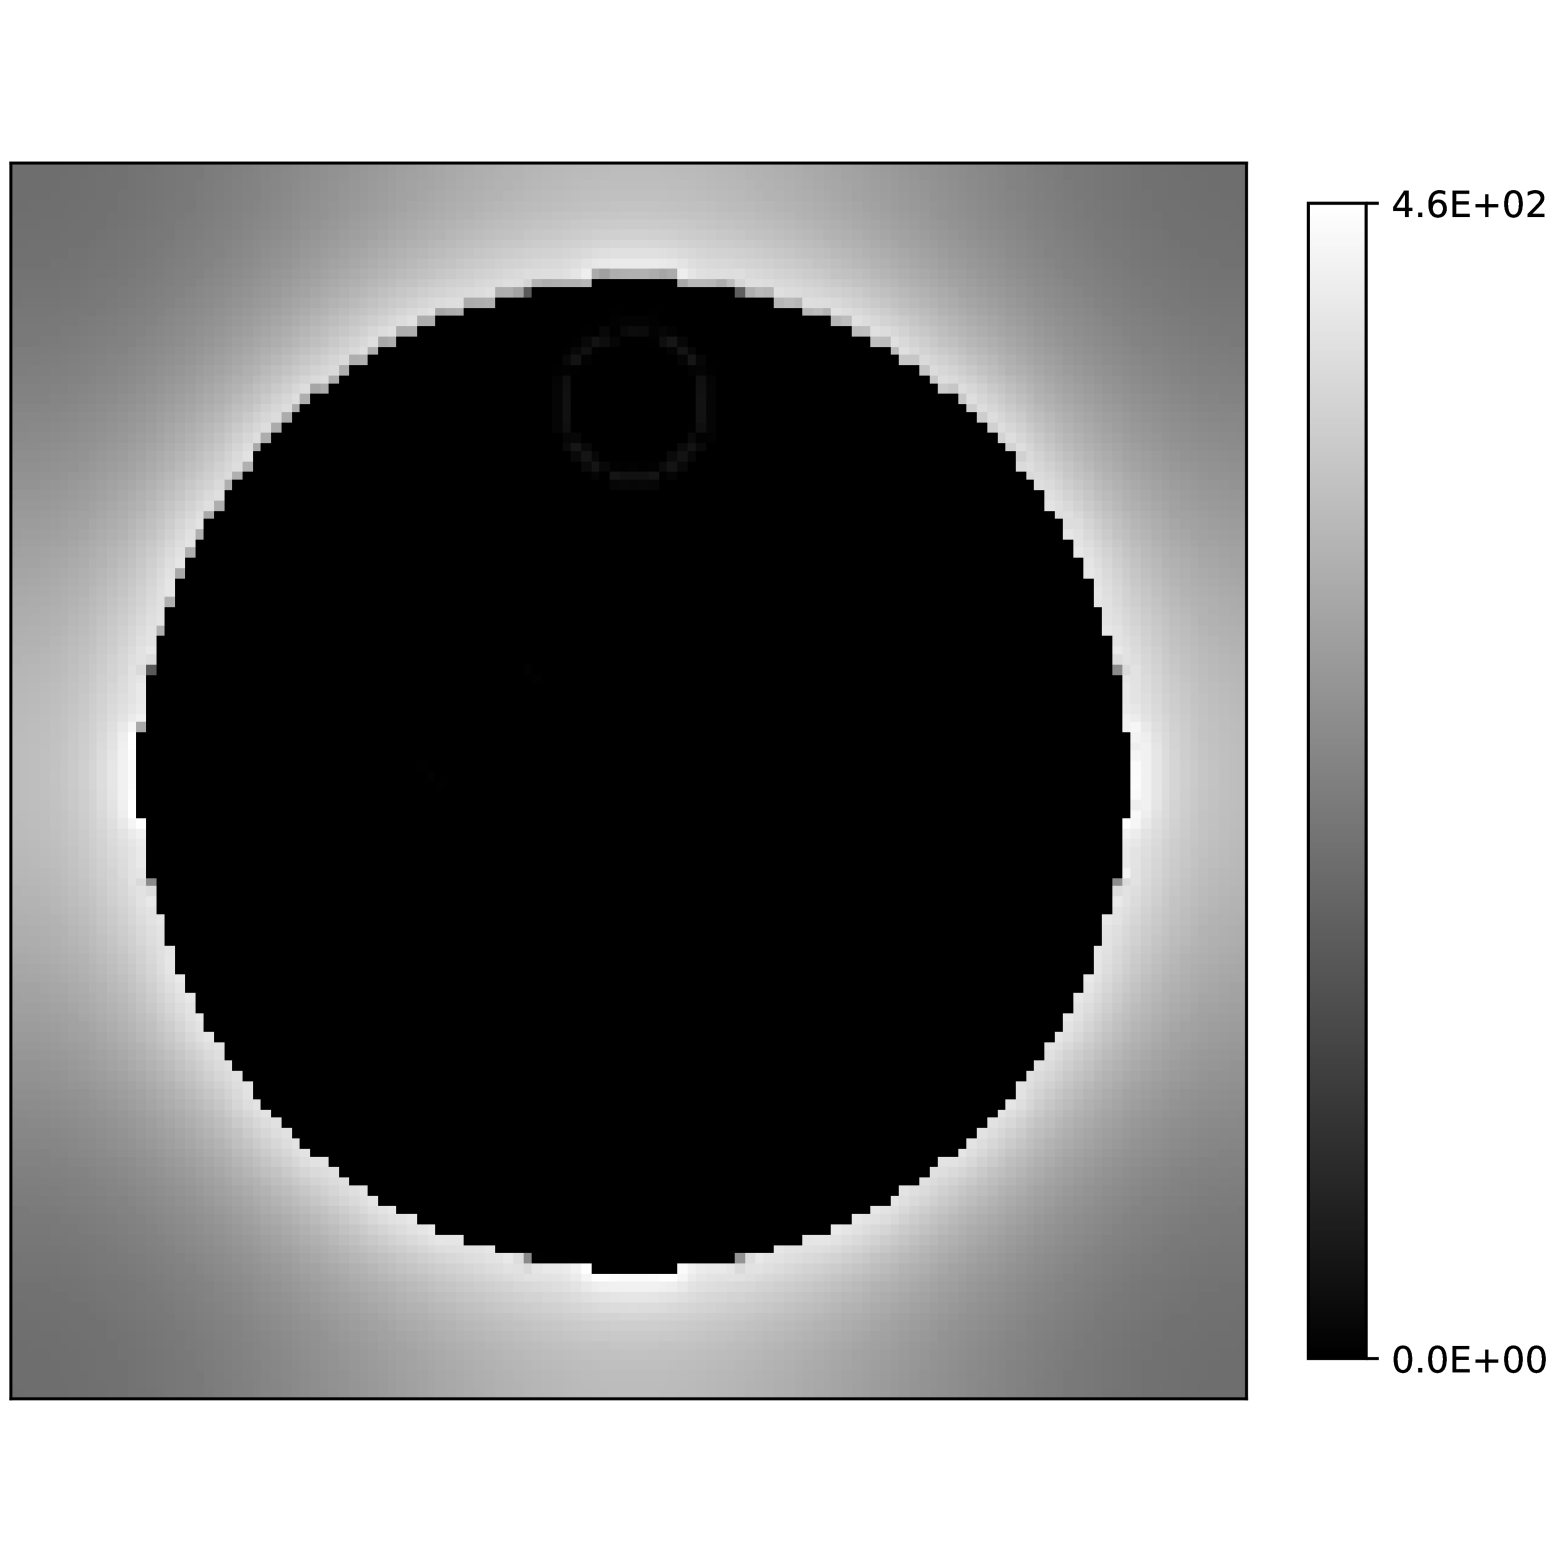

The fact that there is a neighborhood of around which the residual has positive curvature is critical to have local recovery conditions. We can compute this radius explicitly when the true parameters are known. We do this for a water, fat and silicone in silico phantom (see Section 5.3 below) and we evaluate the bounds that we provided for this radius in Theorem 3.1. Fig. 1(e) shows

for every voxel in the image. This quotient decreases by 50% in a range between Hz to Hz and reaches zero by to more than 60Hz. This shows that the curvature of the residual can vary significantly between voxels. Fig. 1(f) shows the radius at which the value attains 50% of its value, illustrating the spatial dependence on the signal at each voxel. Fig. 1(g) shows the estimates found by the bound in Theorem 3.1. As discussed earlier, it severely underestimates the radius, attaining a maximum value of Hz. In contrast, in Fig. 1(h) we show the estimate found using the improved bound in (31). As can be seen, although it still underestimates the radius, it provides a bound of Hz.